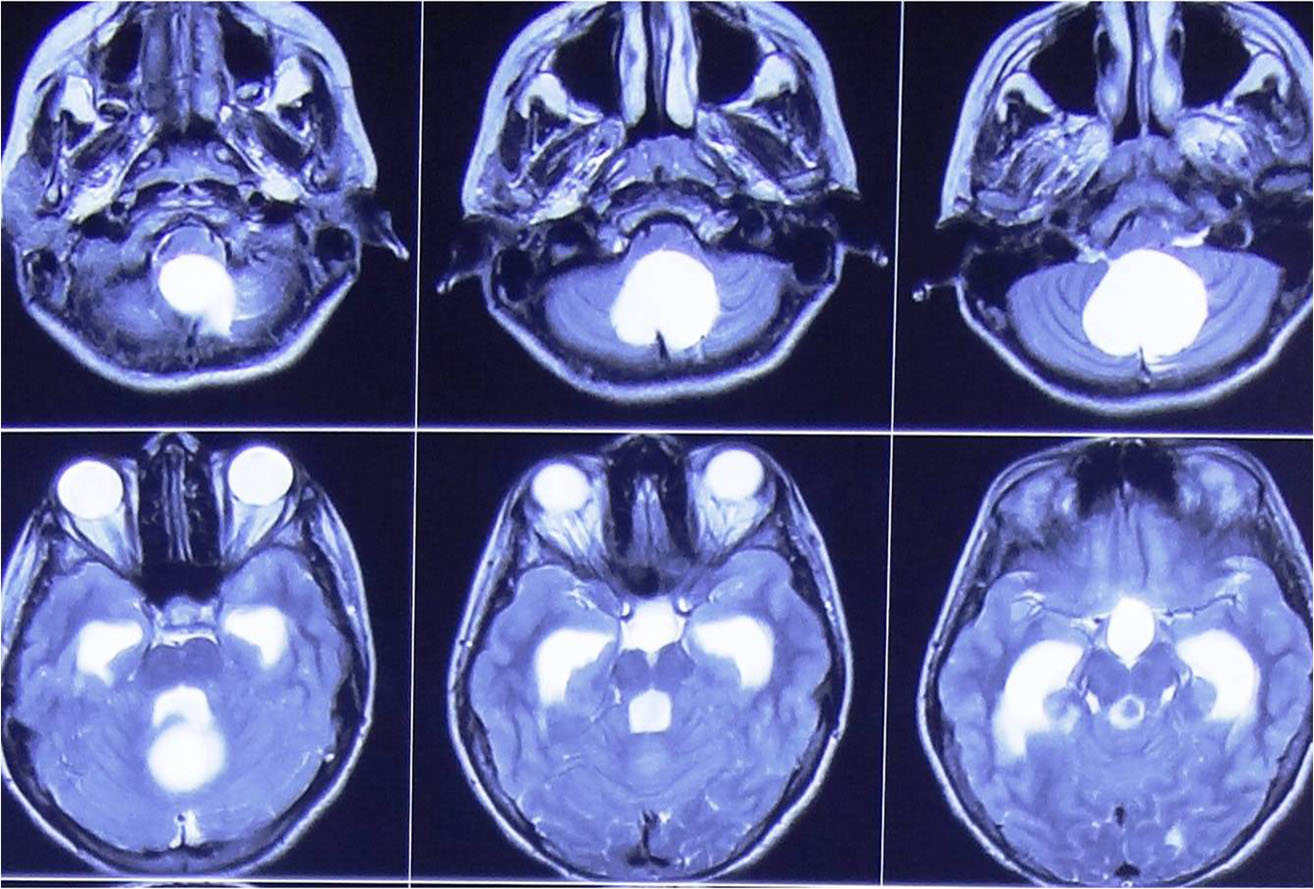

any of these symptoms he/ she should consult a neurosurgeon immediately. Usually CT Scan/ MRI of brain help

in the diagnosis. Most of the brain tumours can be safely treated by surgery but the treatment plan may vary